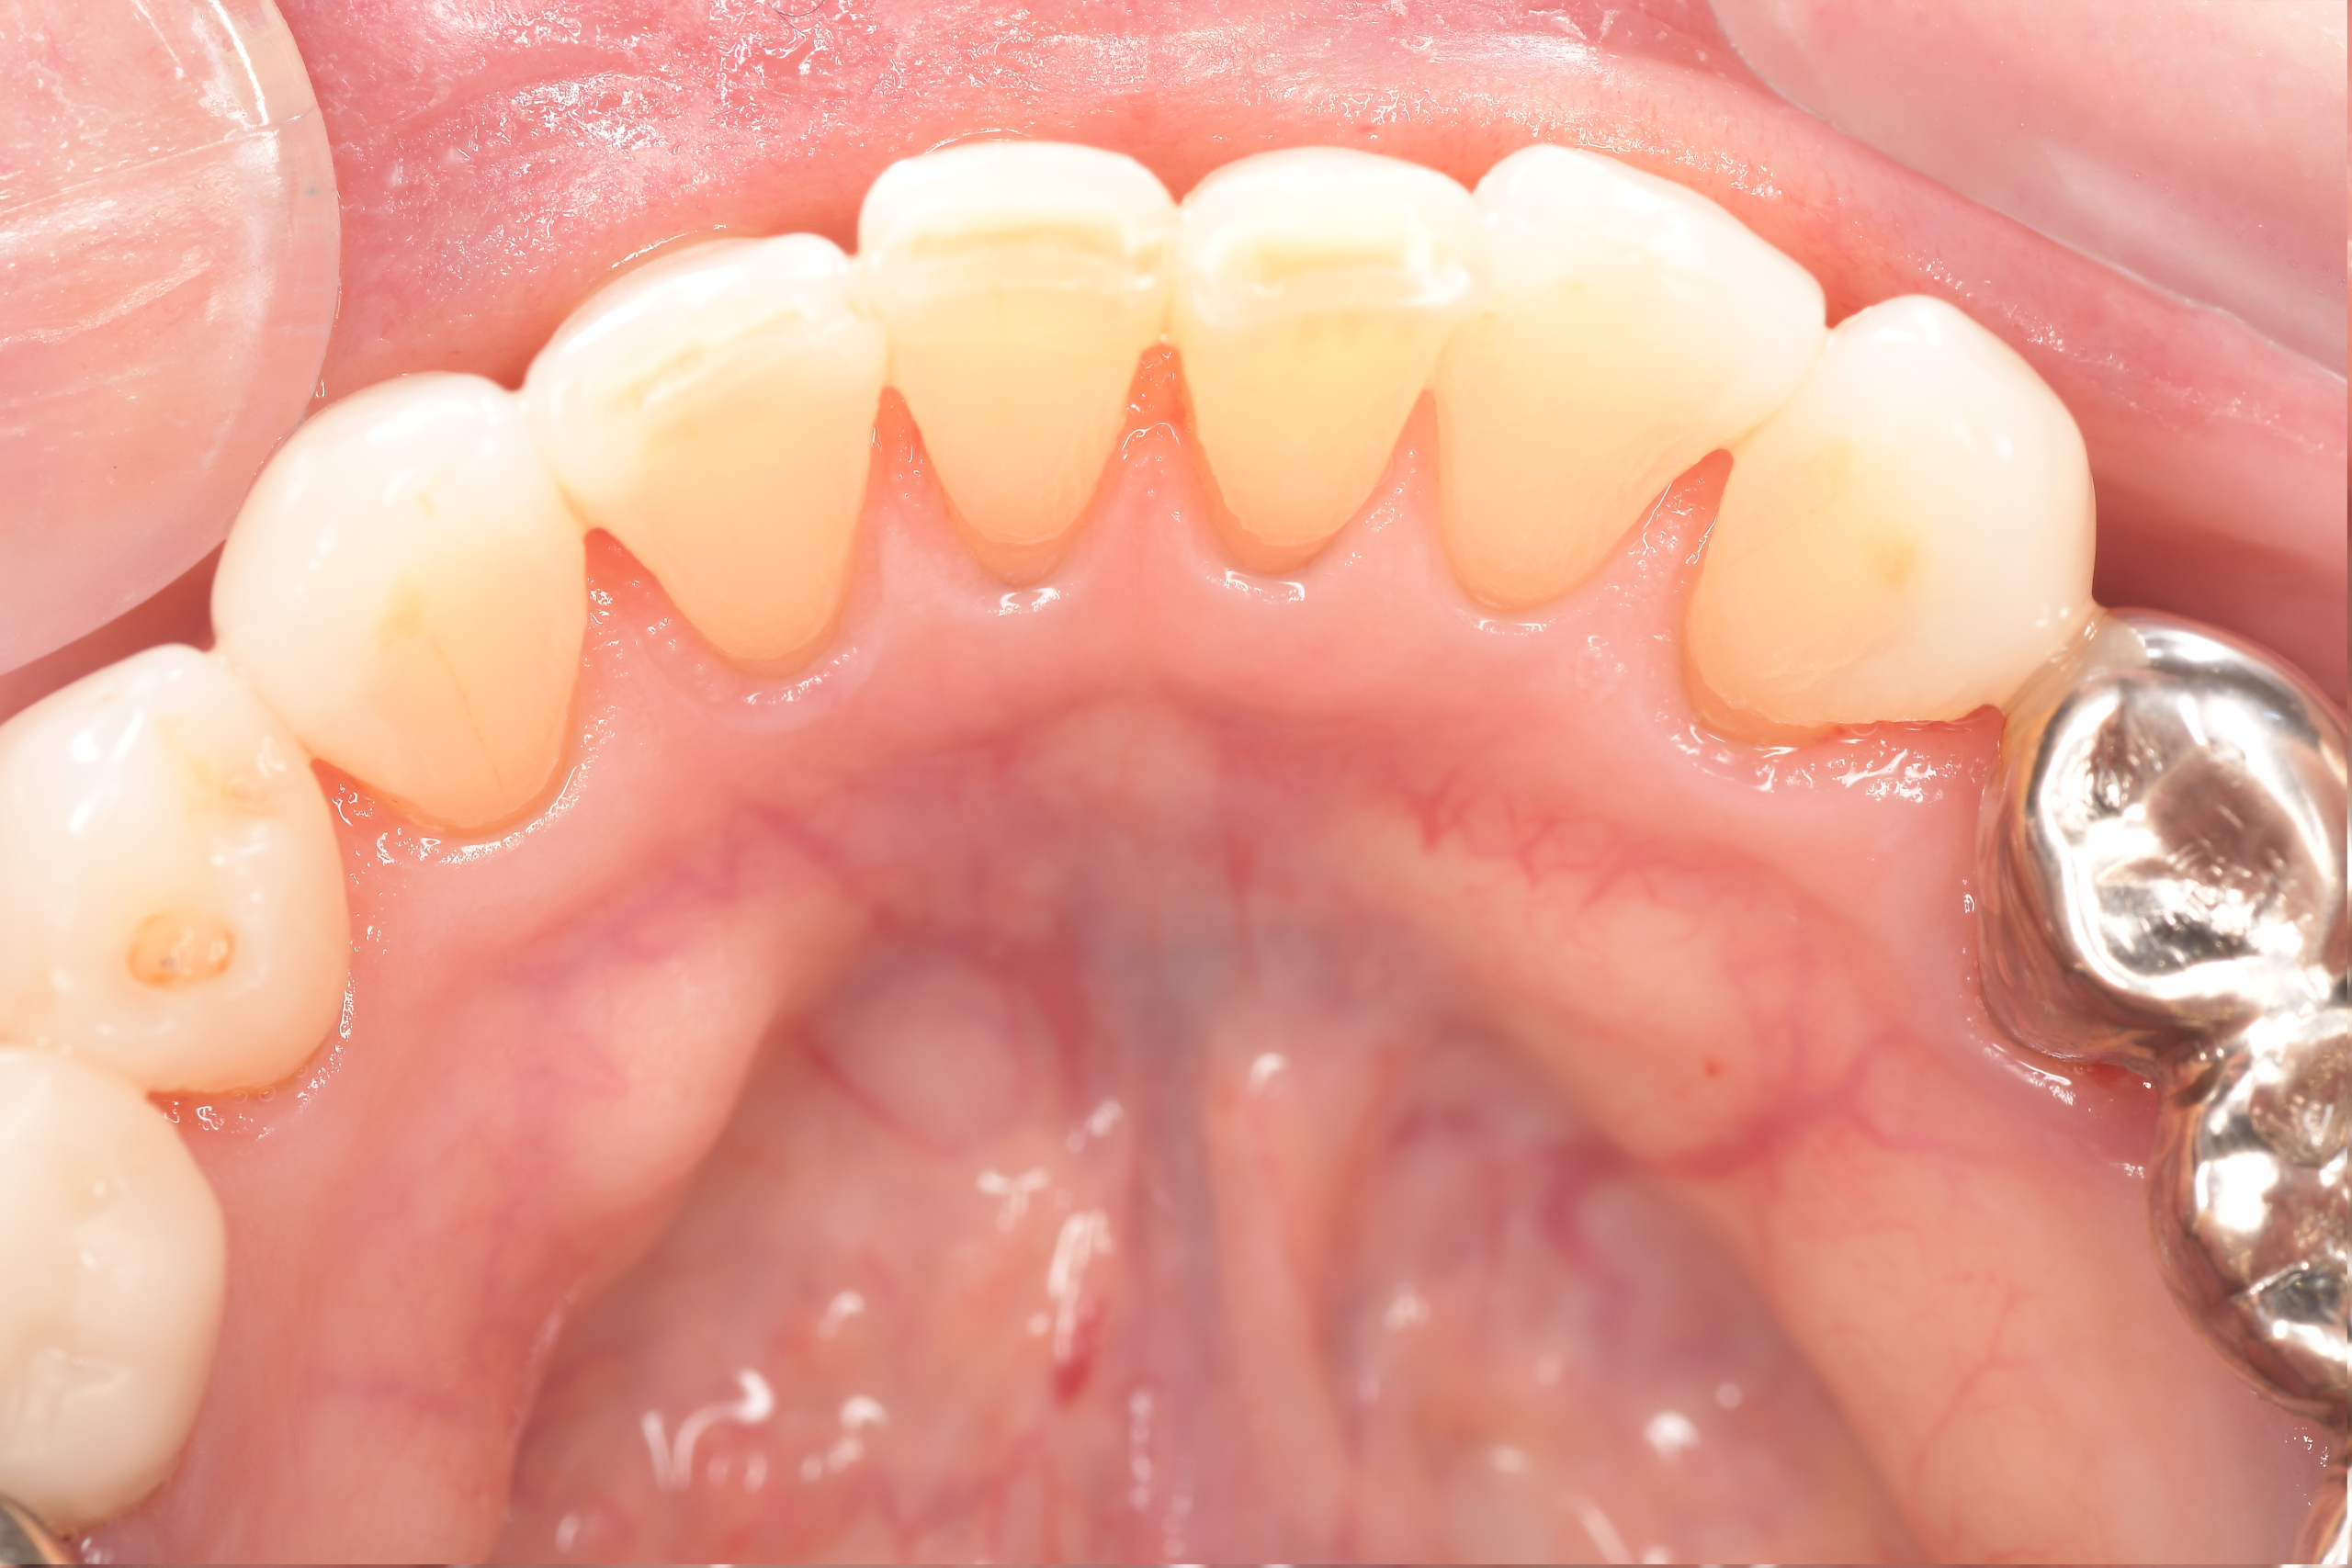

クリーニングの症例

現在の治療費と異なる場合がございます。最新の治療費は料金表をご確認ください。CASE 1

Before

After

基本情報

| 主訴 | 見た目をきれいにしたい |

| 治療期間 | 6ヶ月 |

| 治療費 | ジルコニアボンド(セラミックの被せもの)¥165,000×7(税込み) オフィスホワイトニング4回 ¥4,400×4(税込み) ホームホワイトニング¥11,000 |

| リスク・副作用 | かみ合わせがとても強い方の場合、稀に割れてしまうことがあります。 |

| 先生からの提案 | 上の前歯6本と右下の2番目の歯はセラミックの被せもので治療。 残りの下の前歯5本はプラスチックの材料で虫歯を治療し、 ホワイトニングをおこないました。白くなったご自身の歯の色に合わせてセラミックの 被せものを作成しています。 模型上で完成後をシュミレーションし、上の歯茎の位置をきれいに見えるように 揃えています。(外科処置はしていません) |